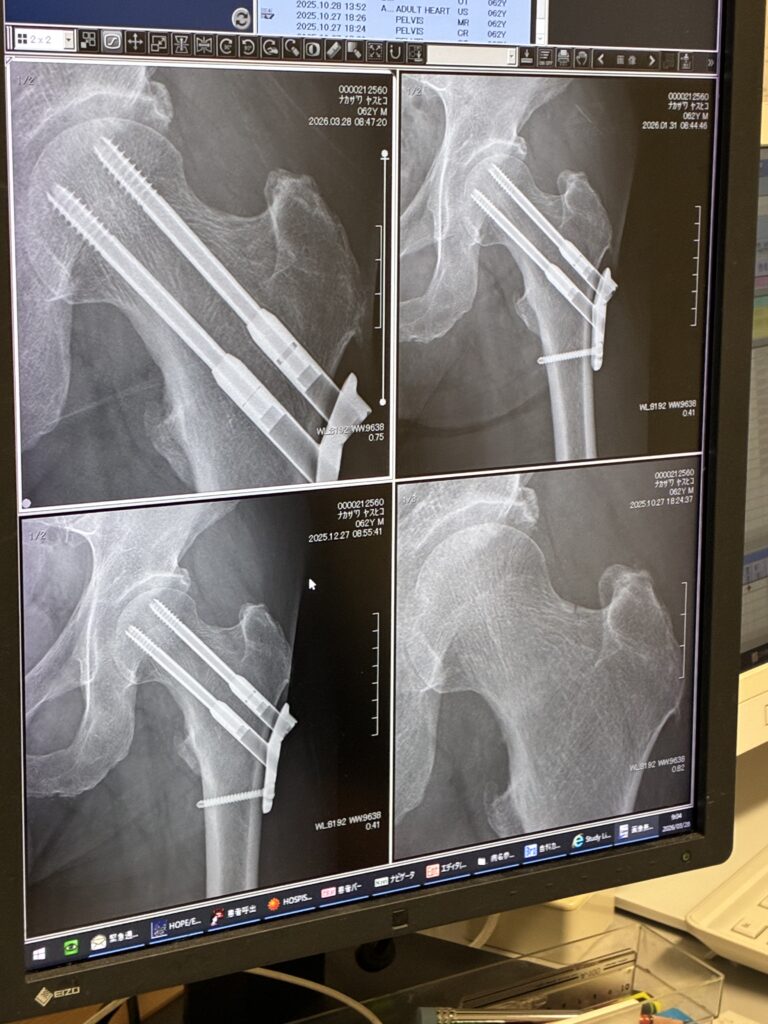

手術後5か月の検診に行ってきました。

レントゲンを撮って、手術をしてくれた先生に経過を観察してもらうわけだけど、骨折部はきちんとつながっているので、運動も普通にして良いと言ってもらえました。

ただし、大腿骨警部が疲労骨折をするなんてそもそもとても珍しいことらしいです。なので先生は僕がよっぽど無茶をする奴だと思っているみたいで「くれぐれも無理しちゃダメ。軽く運動する程度にしておきなさい。」と念を押されました。そして次回は3か月後に経過を見せに来るようにと指示されましたが。とにもかくにも運動の許可をしてもらえたのは良かったです。